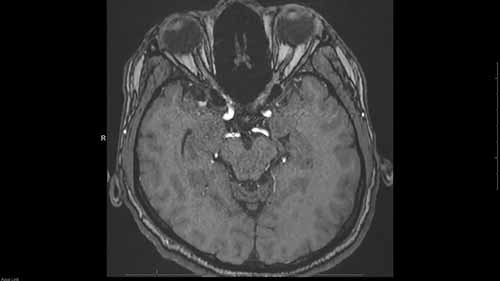

头部磁共振血管造影

头部磁共振血管造影常用于评估大脑血管,包括颈动脉、椎动脉和Willis环。这段视频介绍了评估头部MRA的方法。